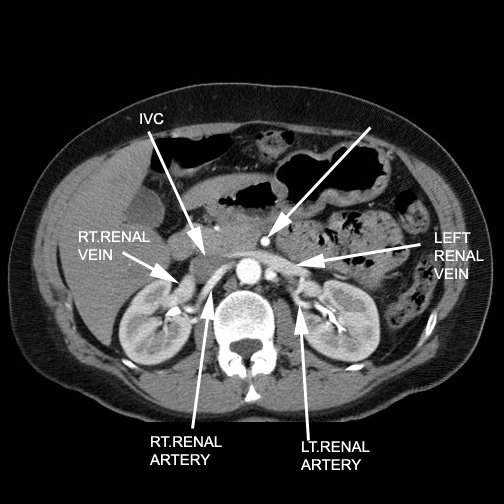

- Right renal artery passes behind the

IVC, Rt renal vein & head of pancreas.

- Left renal artery lies behind the body

of the pancreas, Lt renal vein and splenic vein.

- Right renal artery is longer, passes

behind

- inferior vena cava

- right renal vein

- head of pancreas

- Left renal artery is slightly higher and

lies behind

- body of pancreas

- left renal vein

- Splenic vein